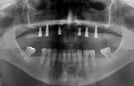

Tomogafia computadorizada, para analise ossea e escaneamento, para planejamento dos futuros dentes